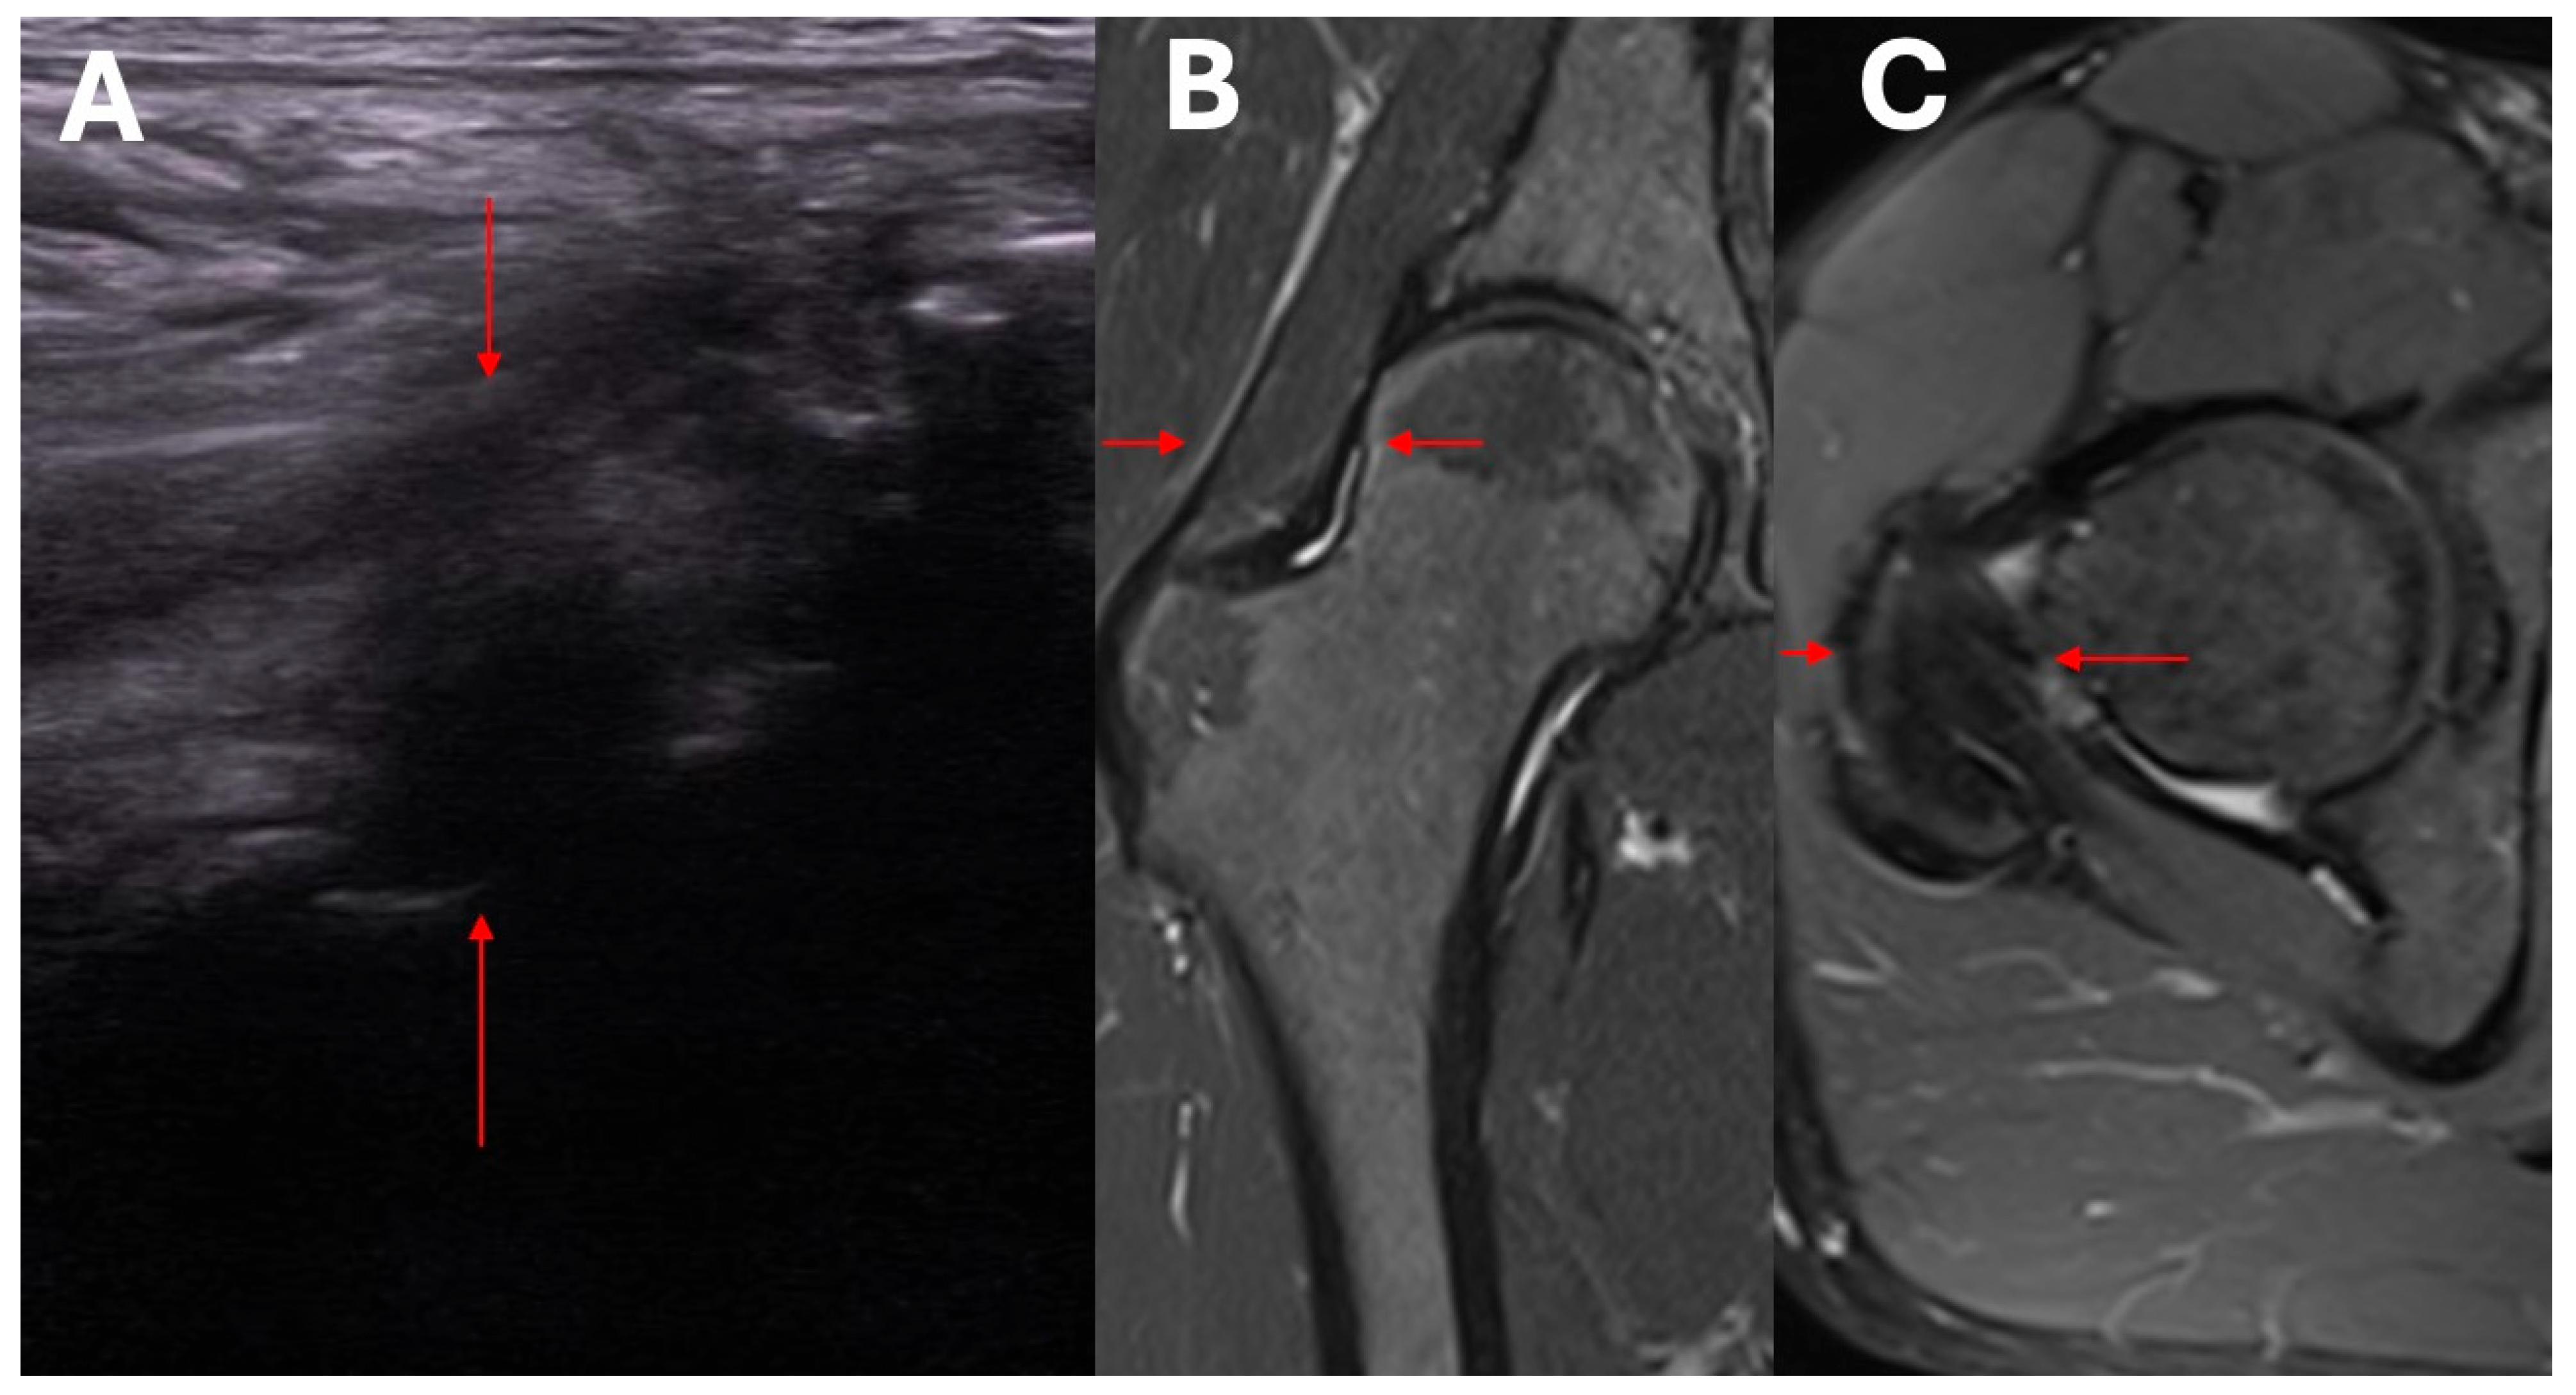

- Ultrasound assessment of hip morphology, and radiologic imaging with MRI where necessary.

- Clinical and ultrasound assessment to identify local pathological mechanisms underlying symptomatic HOA.

- Assessment of structural changes using imaging studies.

- Exclusion/confirmation of intracapsular and extracapsular inflammation based on ultrasound imaging.

- Clinical and ultrasound assessment of the intracapsular, extracapsular, anterior, anteromedial, lateral, and posterolateral aspect of the hip.